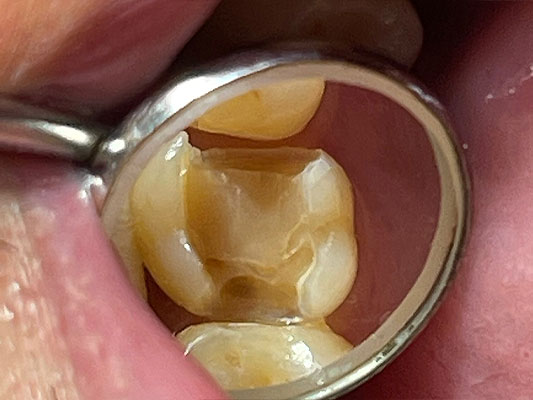

虫歯治療前

この患者さんもマウスピース矯正中に虫歯治療の必要があり、左上6番の虫歯治療することになりました。デジタルの歯科治療に豊富なノウハウを持つ恵比寿・広尾歯科はマウスピース再製作の費用や矯正期間遅延の心配することなく、矯正中も虫歯治療をおこなうことができます。

虫歯治療治療に際して、矯正用マウスピースの再製作(時間と費用がかかり矯正計画が大きく遅延します)を避けるために、マウスピース作製時の歯型と同じ形で虫歯治療をする必要がありました。恵比寿・広尾歯科は黎明期から口腔内デジタルスキャナー(光学印象)を導入し、デジタル技術の蓄積があるため治療後の修復物をセラミックで作る場合は、現在の歯とまったく同じ形態で作成することで矯正用マウスピースに影響なく虫歯治療とマウスピース矯正が可能というご提案を差し上げたところ同意を頂き治療をおこないました。

治療ステップ2形成と印象

すべての虫歯を慎重に取り除きます。薄くなった歯質を丁寧に補強し、口腔内デジタルスキャナー(光学印象)でデジタルの歯型採りをおこないます。処置後は仮の蓋をして、この日の治療は終了となります。デジタルによる型取りで治療した窩の形を、マウスピース作製時の型取りでは歯の形(外形)をそれぞれデジタルで処理することで、矯正用マウスピースを再製作することなく精密な詰めもので治療することができます。

治療ステップ3セラミックの詰めものをセット

デジタル制御で削り出したセラミックの適合をチエックします。試適で問題がない場合はセラミックの詰めものをセットして治療は終了となります。ご覧のとおりもともと作成していた矯正用マウスピースに外形がぴったりと合って、再製作の必要がないことがお分かり頂けるとおもいます。